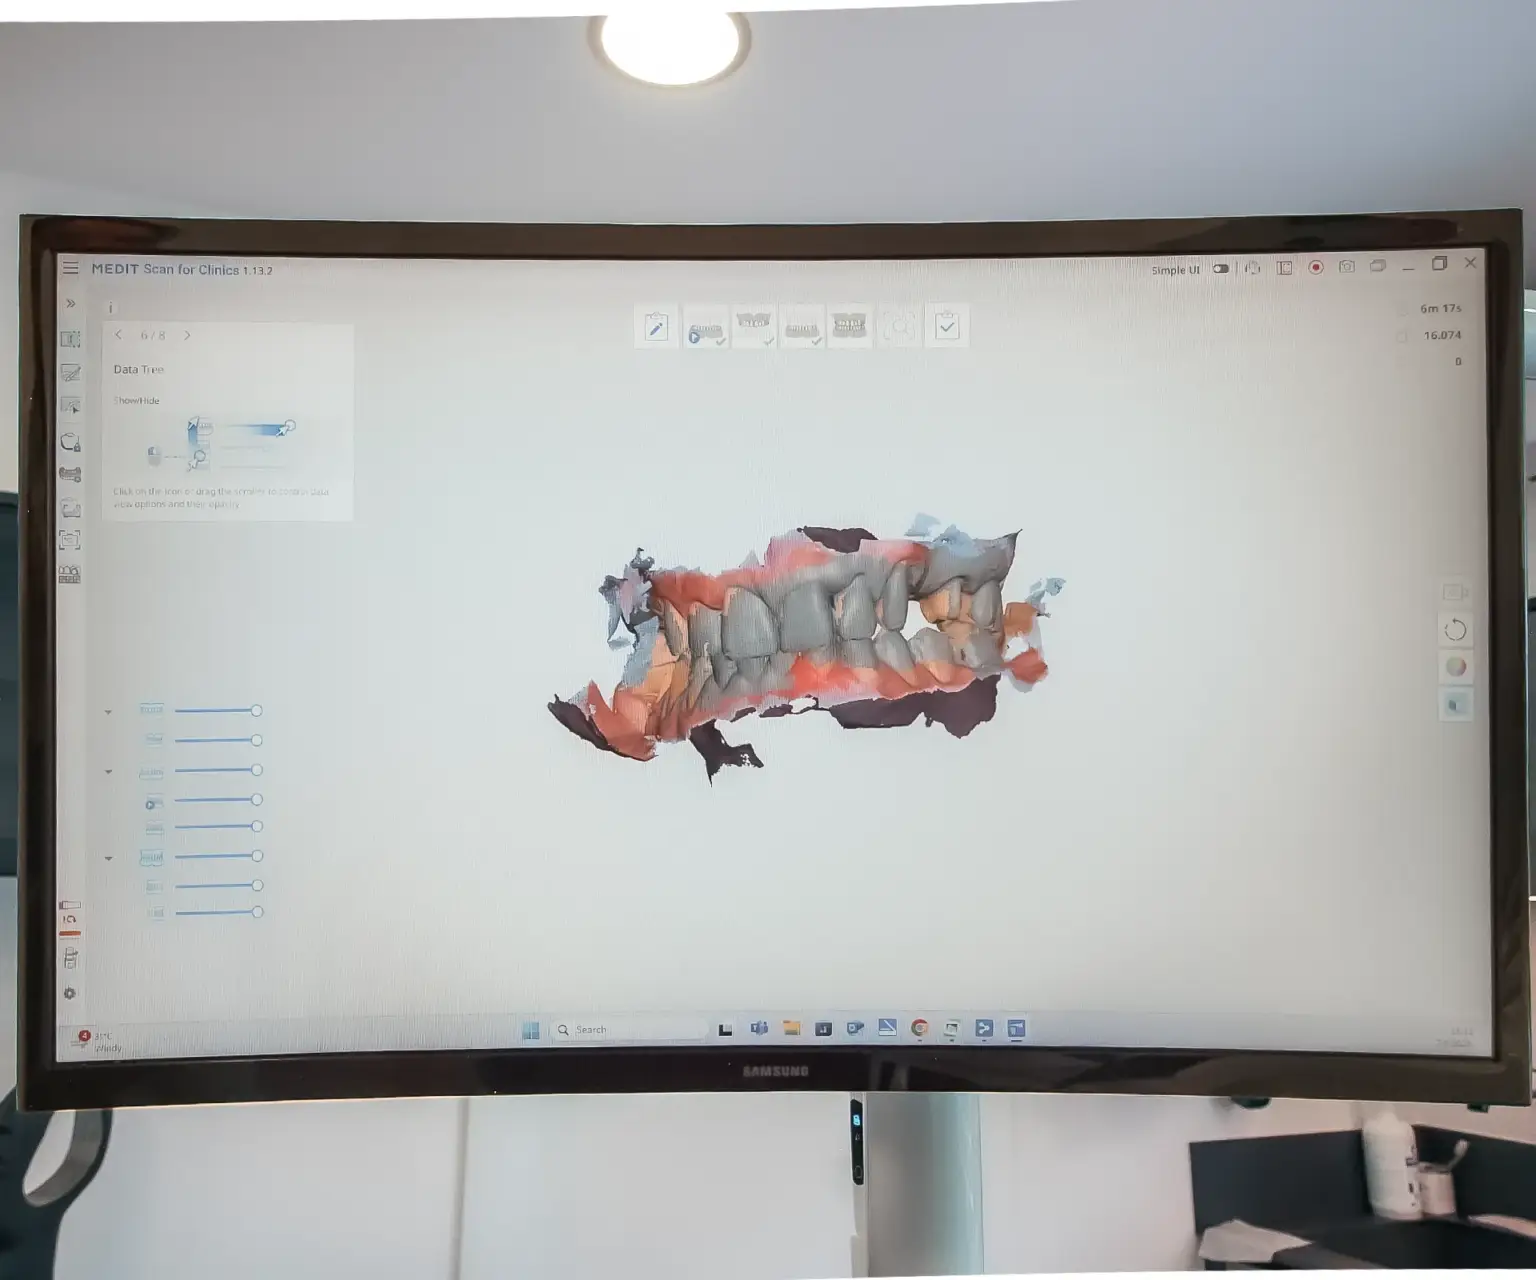

Intraoralni skener

Zaboravite na neugodno uzimanje otisaka pomoću klasičnih masa – intraoralni skener donosi revoluciju u dentalnoj dijagnostici. Umjesto fizičkih otisaka, koristi se digitalno skeniranje usne šupljine koje je brzo, precizno i maksimalno ugodno za pacijenta.

Ova metoda je posebno pogodna za osobe s osjetljivim refleksom na povraćanje jer ne zahtijeva kontakt s nepcem ni dubljim dijelovima usne šupljine. Skener omogućuje visoko precizne 3D prikaze zuba i zubnog luka, što značajno olakšava planiranje protetskih radova, ortodontske terapije i drugih zahvata.

Intraoralni skener doprinosi bržem postupku, smanjuje mogućnost pogrešaka i pruža bolje iskustvo za pacijenta.